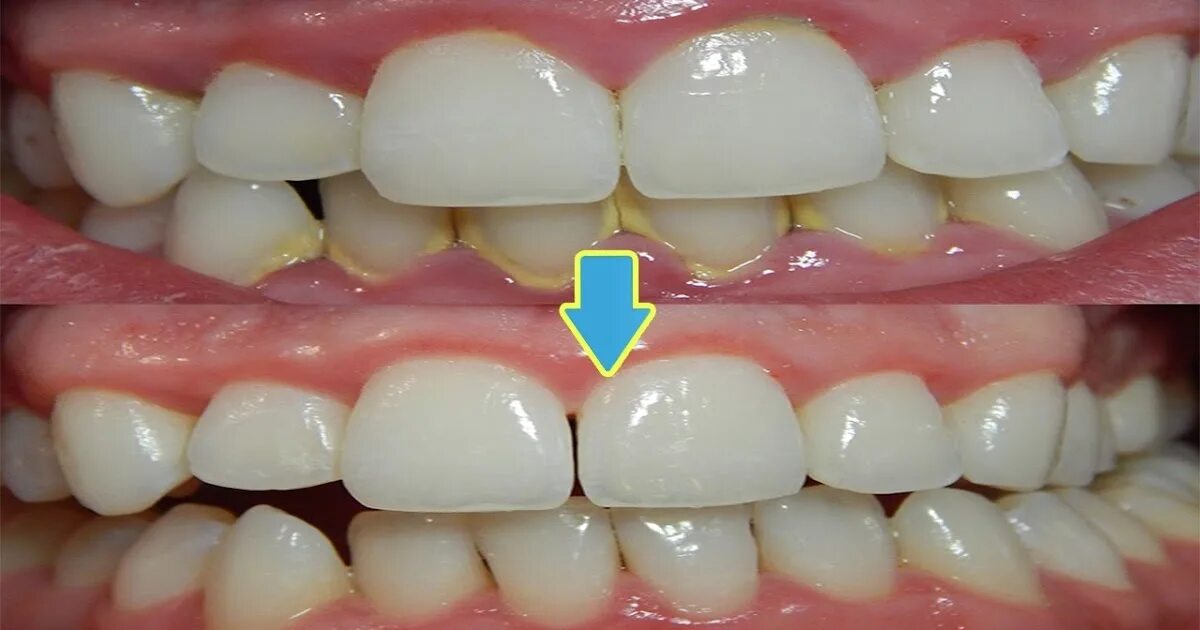

Матрица гаряева зубы и десна